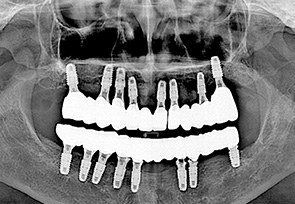

before

after